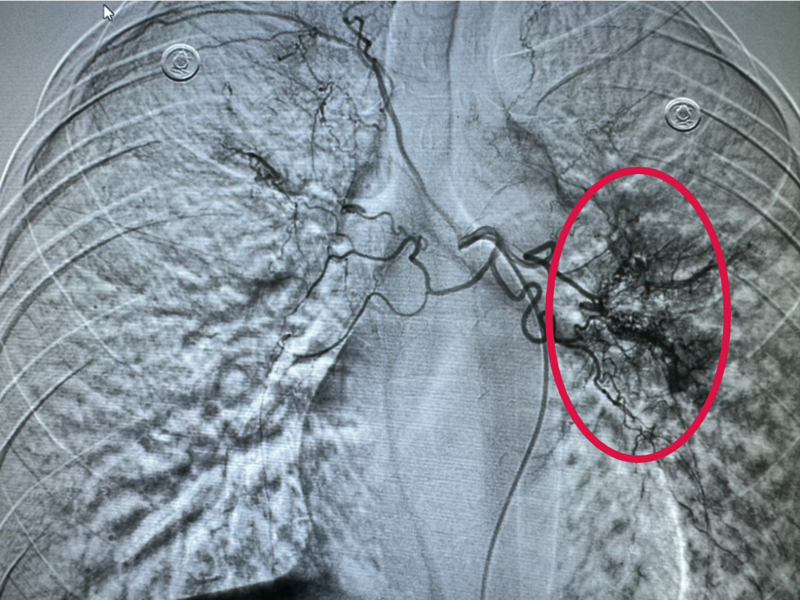

造影下,可见出血位置,出血量大

当天凌晨1点,在病房休息的张某突发大咯血,咯血量已超300ML,特别危险的是患者在咯血中极易造成气管堵塞,一旦发生意外,患者窒息死亡。呼吸内科黎晓萍主任接到科室急救电话后立即赶到病房,病情危急,做完评估,见过大风大浪的她当机立断,马上联系肿瘤科郑立刚主任前来紧急会诊,会诊后,决定在大C臂下为患者做经导管双侧支气管动脉造影术+动脉栓塞术,紧急为患者封堵出血血管,让其停止咯血,后立即把患者送入介入室开展介入急诊手术。手术成功把出血血管封堵缺口,患者也停止咯血,这时,所有人才放下了悬着的心。